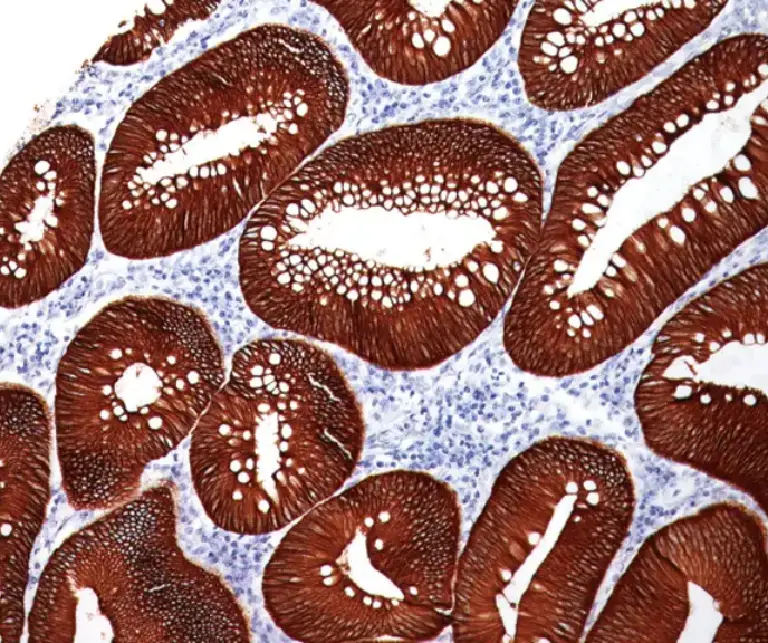

Gastrointestinal (GI) Pathology